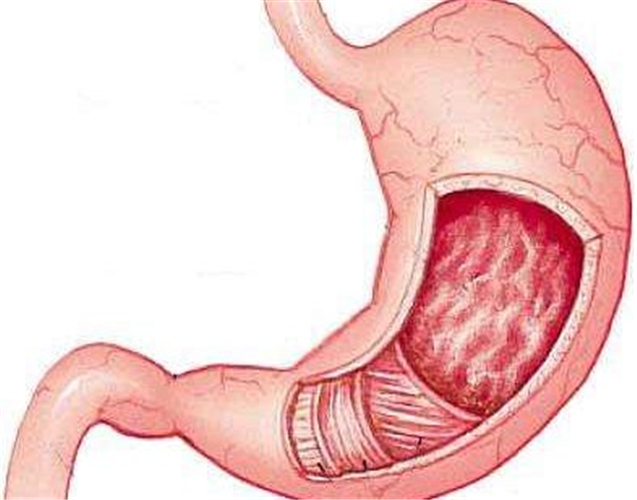

急性胃炎

急性胃炎胃部